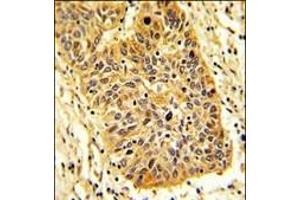

RIOK1 antibody (N-Term)

The Rabbit Polyclonal anti-RIOK1 antibody is suitable to detect RIOK1 in samples from Human. It has been validated for WB and IHC (p).

Western Blotting (WB), Immunohistochemistry (Paraffin-embedded Sections) (IHC (p))

This RIOK1 antibody is generated from rabbits immunized with a KLH conjugated synthetic peptide between 126-156 amino acids from the N-terminal region of human RIOK1.

WB: 1:1000. WB: 1:1000. IHC-P: 1:50~100